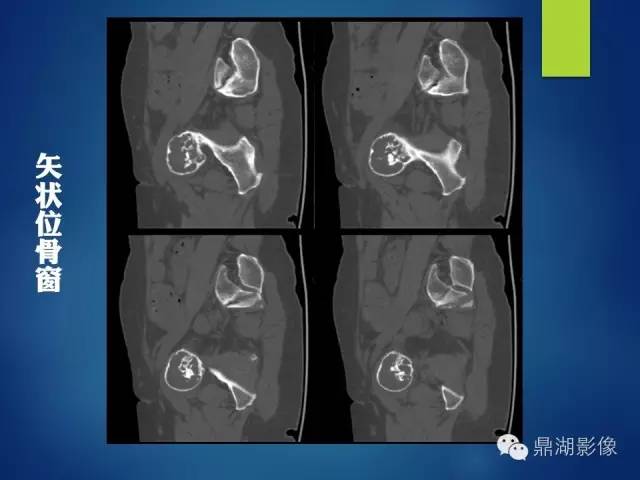

影像表现:

左侧耻骨可见一不规则略低于软组织密度影,周围骨皮质变薄,其内可见丝瓜囊样密度增高影,未见明显骨膜反应及骨折线。

X 线表现为侵蚀骨质破坏,可见软组织肿块。CT 能更清楚地显示其钙化,但不广泛。肿块含水量多,故在CT像上表现为低密度;黏液型软骨肉瘤较普通型软骨肉瘤更常见出血,在MRI的T1WI、T2WI 上均表现为高信号, (肿块) 增强扫描肿块呈轻度强化。